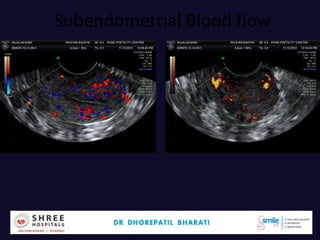

Subendometrial Blood flow

Dr.Bharati Dhorepatil 43